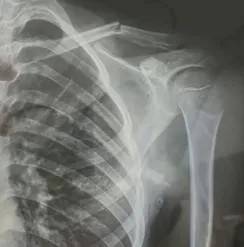

10月30日,内蒙古自治区赤峰市宁城县苏木皋小学一学生家长贾女士给记者打来电话,介绍了孩子被打的原因虚拟币JT。贾女士称,放学通道的墙上有一个电灯的开关,好多孩子放学时都随手去拨弄开关。出于安全考虑,学校和老师都禁止孩子拨弄开关。23日放学时,他儿子和另一个同学调皮,再去拨弄了那个开关,被正在值班的另一个班的班主任发现,把她儿子打了,且打骨折了。

图片由报料者提供